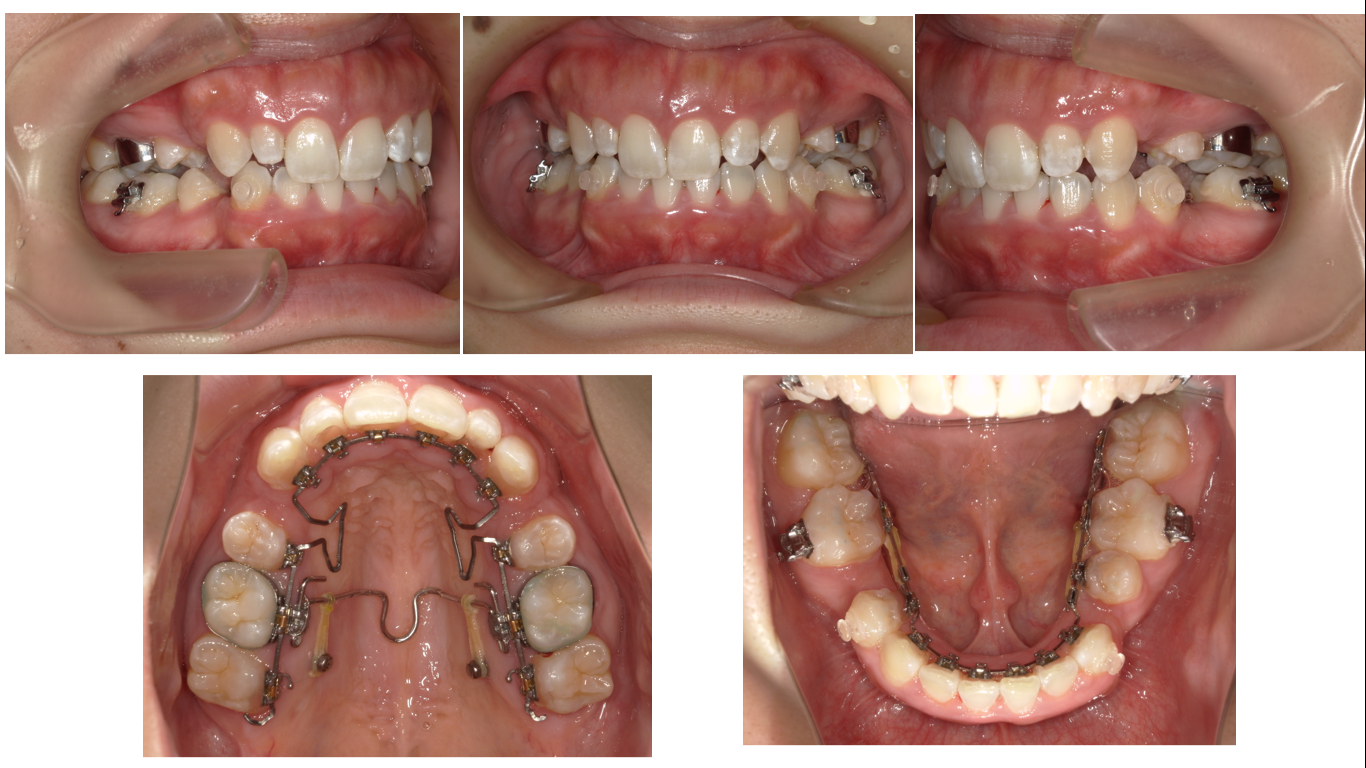

矯正症例143 AngleⅡ級2類、裏側矯正、舌側矯正

治療開始年齢24歳、治療期間3年、抜歯部位:下顎左右5番、上顎左右4番、治療費総額1,310,000(税込み)